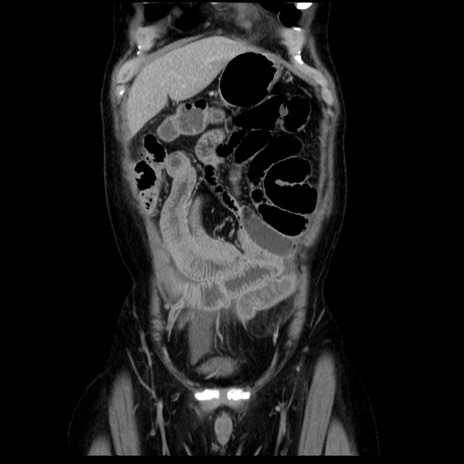

症例29(冠状断像)

【症例】40歳代男性

【現病歴】2日前から胃痛あり。徐々に周期的な激痛に変化した。本日になっても激痛があるため受診。

【身体所見】意識清明、BT 38-39℃台あり、腹部:膨満、やや硬、右下腹部に圧痛あり。

【データ】WBC 8500、CRP 23.26